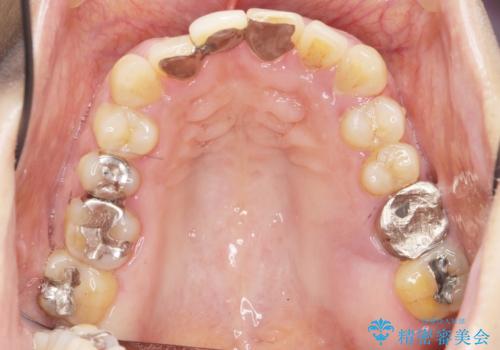

歯周病に対する全体治療

- 近医で「重度の歯周病です、入れ歯にする必要がある。」、と言われ入れ歯以外の方法がないか相談にみえられました。

再生治療、歯周外科を行うことで歯周病治療を行い、残すことのできる歯の歯周環境を整える。

残すことのできない歯は抜去したのち骨造成を含めたインプラント治療を行い、しっかりとした咬合関係を確立していきます。

治療期間はかかりましたが、しっかりと歯周病治療・インプラント治療を行ったおかげで歯周病の状態は非常に良くなり、安定した咬合関係を確立することができました。